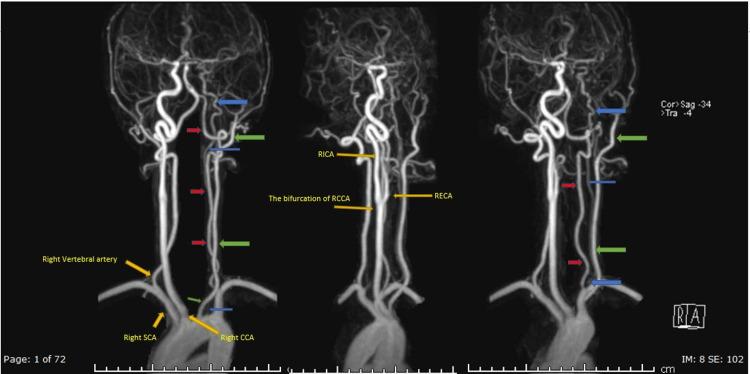

The agenesis of the left common carotid artery, with independent origins of the external and internal carotid arteries from the aortic arch, is a well-described but extremely rare congenital anomaly. We present a case of agenesis of the left common carotid artery with the independent origin of the left internal and left external arteries from the arch of the aorta in a patient with ankylosing spondylitis which was depicted by CT angiogram and magnetic resonance angiography. The diagnosis of this anatomical variant especially before interventional procedures is of great importance, as it could complicate the catheterization of these arteries.

左颈总动脉缺如,颈外动脉和颈内动脉分别独立起自主动脉弓,是一种已被充分描述但极为罕见的先天性异常。我们报告一例患有强直性脊柱炎的患者,其左颈总动脉缺如,左颈内动脉和左颈外动脉分别独立起自主动脉弓,通过CT血管造影和磁共振血管造影得以显示。诊断这种解剖变异,尤其是在进行介入操作之前,非常重要,因为这可能会使这些动脉的插管复杂化。